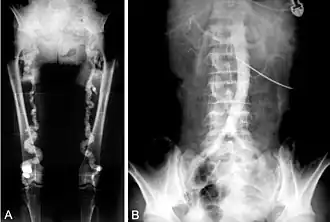

B. Translumbar aortography shows near-total obstruction of the femoral arteries in a patient with Monckeberg's arteriosclerosis.